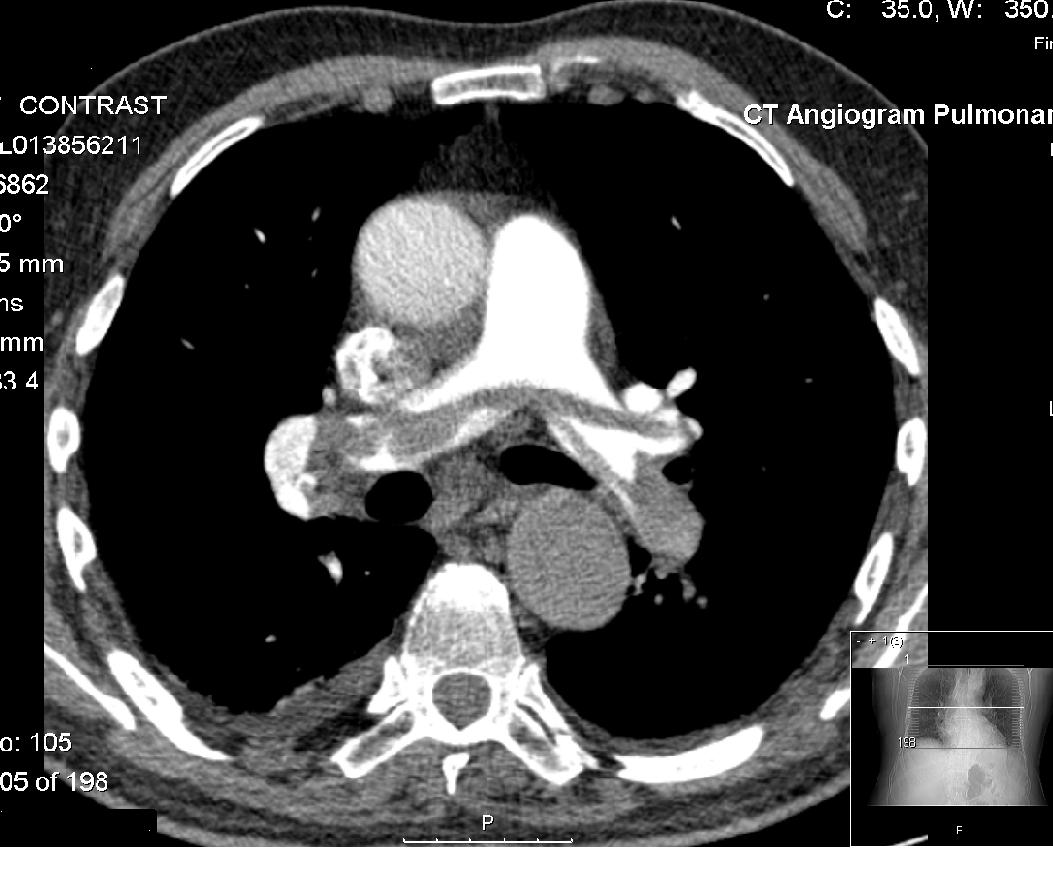

آمبولی ریه

آمبولی ریه زمانی اتفاق می افتد که هر نوع جسم خارجی داخل شریان ریوی یا یکی از شاخه های آن گیر کند و مانع جریان خون داخل شریان های ریوی گردد. در اغلب موارد جسم خارجی عبارت است لخته خونی که از سیاهرگ (ورید) های پا کنده شده و در عروق ریه گیر می کند. ندرتا مواد دیگری مانند چربی هم می توانند موجب آمبولی ریه شوند.